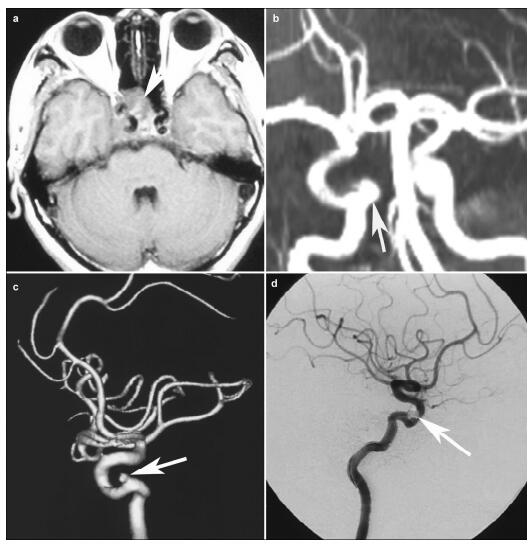

20170308101841  Figure 1 MRI and DSA of the patient. a: MRI shows a lesion locating at the saddle area and invading right cavernous sinus (arrow). b: The MRA 4 months after gamma knife shows a suspicious aneurysm (arrow). c: Three-dimensional DSA confirms the existence of the aneurysm (arrow). d: DSA image after the embolization shows that the treatment effect is satisfactory (arrow).